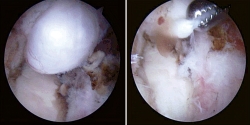

Presentamos el caso de un varón de 48 años, instructor de tenis profesional, sin antecedentes clínicos relevantes. Consulta por coxalgia izquierda incapacitante durante la actividad laboral de unos 18 meses de duración. El examen físico mostró dolor en flexión y rotación interna de la cadera izquierda y una prueba de choque positiva. Se realizaron radiografías para evaluar la presencia de morfologías que pudieran predisponer a un pinzamiento femoroacetabular (Figura 1). No se observó morfología anormal o signos de osteoartritis. El tratamiento inicial incluyó la prescripción de antiinflamatorios no esteroideos (AINE) y la modificación de la actividad física. Se realizó una resonancia magnética (RM) para completar el estudio. Los resultados de la RM no identificaron alteraciones morfológicas o cambios de señal en la cabeza femoral que pudieran sugerir necrosis ósea, focos de osteocondritis, fracturas por estrés, edema óseo u osteoporosis transitoria. Se identificó una lesión del labrum anterior con un quiste paralabral asociado a esta, de 32 × 17 mm (Figura 2). Después de 3 meses de tratamiento conservador sin mejoría clínica, se propuso la escisión quirúrgica y la reparación del labrum. La extirpación quirúrgica se realizó a través de artroscopia mediante técnica fuera-dentro. Todas las estructuras óseas en el compartimento central no mostraron signos patológicos. Se observó una lesión del labrum en su zona anterosuperior (zona 2)(2). En el compartimento periférico, se identificó una gran lesión quística que rodeaba el borde anterosuperior del labrum y el acetábulo (Figura 3). La extirpación completa del quiste se realizó artroscópicamente utilizando material específico para la artroscopia de cadera. No se registraron complicaciones intraoperatorias. La reparación labral se realizó con un sistema de anclaje All-Suture® de tipo Y-Knot® (Conmed). Se inició el protocolo de fisioterapia postoperatoria habitual de nuestro centro, permitiendo la carga parcial con dos muletas al momento del alta con progresión gradual a peso completo en un periodo de 2-3 semanas, seguido de un protocolo de rehabilitación para conseguir el rango completo de movilidad articular y lograr la fuerza completa de la extremidad. En un periodo de 3 meses, el paciente regresó por completo a la actividad física. No se observaron complicaciones.

Figura 3. Imagen artroscópica del compartimento periférico. Izquierda, quiste paralabral (a) y cabeza femoral (b). Derecha, resección del quiste.